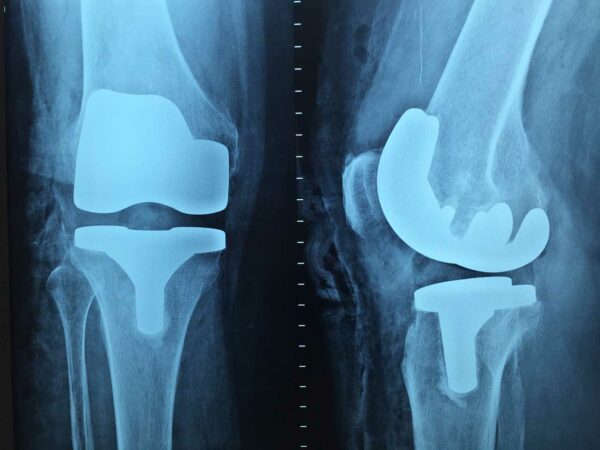

Der Arzt überprüft durch das Verschieben und Bewegen des Knies die Schmerzempfindlichkeit. Hinzukommt, dass er über eine Kniespiegelung (Arthroskopie), Röntgenbilder, Ultraschalluntersuchung oder eine Magnet-Resonanz-Tomographie-Aufnahme (MRT) den Grad der Abnutzung feststellen kann oder herausfinden kann, ob eine Arthrose vorliegt.

Bei heftigen und starken Schmerzen hilft zunächst das Kühlen des Knies. Sobald die Stufe des Knorpelschadens durch einen Orthopäden geklärt worden ist, erfolgt die Behandlung, die meist eine Operation einschließt. Eine Glättung des beschädigten Knorpels ist durch einen kleinen Eingriff gegeben, gleichzeitig können auch störende Stücke direkt entfernt werden.

Große Eingriffe sehen dagegen Knorpeltransplantationen vor. Hierfür wird im Labor ein körpereigener Knorpel vermehrt. Wird so ein Eingriff durchgeführt, folgen danach noch einige Nachbehandlungen wie Physiotherapie, um Muskulatur und Bänder zur Unterstützung des Knies zu stärken. Doch bevor man sich einer Therapie aussetzt, muss das Knie an die sechs Wochen entlastet werden.

Bevor man sich gleich verrückt macht und sich fragt, ob man sich wegen des Knirschens unters Messer legen muss, sei gesagt, dass in vielen Fällen bereits eine therapeutische Behandlung zum Muskelaufbau ausreicht, aber auch das muss in jedem Fall mit dem Arzt besprochen werden. Denn wer seit mehreren Jahrzehnten das Problem mit Knie vor sich herschiebt, wird wahrscheinlich nicht um eine Operation kommen.

Im Falle der Fehleinstellung der X- oder O-Beine sollte ein Arzt hinzugezogen werden, denn unter Umständen wird hier nur eine Operation helfen, in der man eine Korrekturosteotomie durchführt.

Sollte der Meniskus eingeklemmt sein, so wird dies mit der Gelenkspiegelung gelöst. Dabei handelt es sich um eine Operation, in der der Meniskus entweder fixiert oder das eingeklemmte Stück entfernt wird. Wenn der Meniskus allerdings gerissen ist, so ist dies eine schwerwiegende Erkrankung und man kommt um einen komplexeren Eingriff nicht herum.